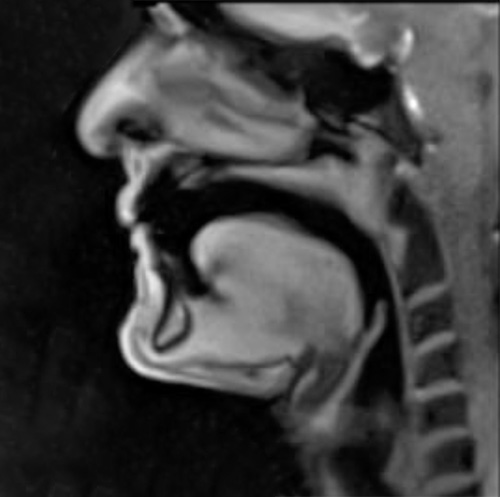

Trombone Science will be launched in 2026. This site will feature real-time MRI (magnetic resonance imaging) videos of Douglas Yeo playing on a specially made trombone manufactured and donated to the MRI project by YAMAHA Corporation, Japan, and commentary by Douglas Yeo and Dr. Peter Iltis. These videos were recorded in 2017 and 2025 at the Max Planck Institute, Göttingen, Germany, as part of the MRI Brass Repository Project. Viewers will see the actual real-time workings of the mouth and tongue (oral cavity/oropharynx), the throat, trachea, and glottis, and the chest and lungs (thoracic cavity) during trombone playing. Trombone Science will show and discuss how human body works during trombone playing throughout the breathing process and when a player produces articulations, slurs, notes in various registers, and more. Trombone Science will also include links to scientific articles based on the work of the MRI Brass Repository Project, and it will provide unique insights for both performers and teachers.